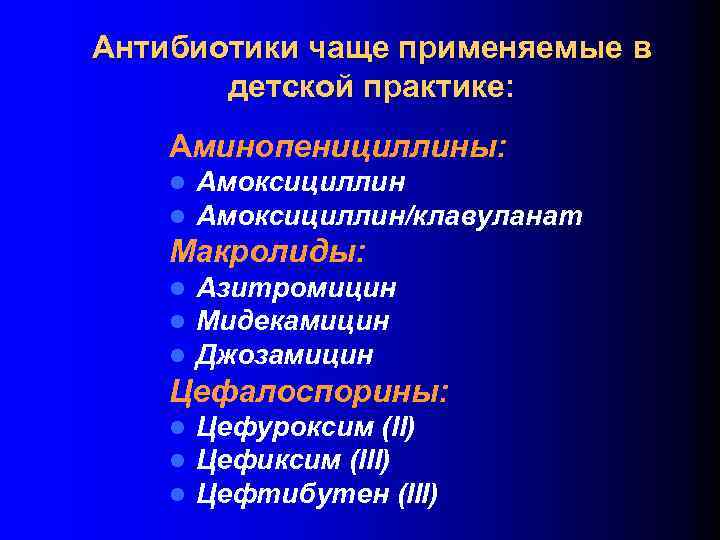

Антибиотики чаще применяемые в детской практике: Аминопенициллины: l l Амоксициллин/клавуланат Макролиды: l l l Азитромицин Мидекамицин Джозамицин Цефалоспорины: l l l Цефуроксим (II) Цефиксим (III) Цефтибутен (III)